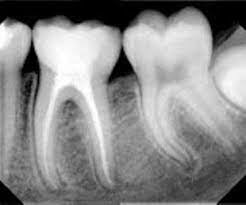

Varios investigadores como Callahan, Grove, Coolidge, Fish y McLean a través de pruebas radiográficas, bacteriológicas, entre otras. Las pruebas radiográficas comprobaron:

1. Que las endodoncias practicadas en la época eran muy deficientes.

2. Que no se podía hacer una endodoncia sin estudios de rayos X

3. Que las lesiones periapicales desaparecían después de hacer un tratamiento endodóntico bien orientado